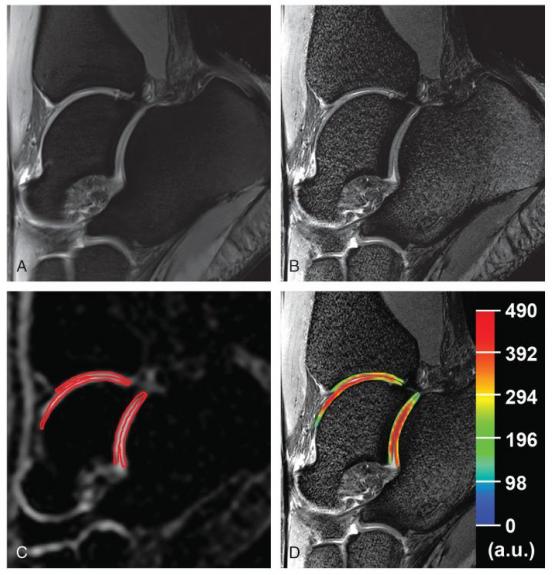

Proton and corresponding sodium images of the ankle joint in a 23-year-old healthy woman. A, Sagittal proton density-weighted 2D-TSE image with fat suppression with lower resolution (0.31 × 0.31 × 3.0 mm3). B, Sagittal proton density-weighted 2D-TSE image with fat suppression (WIP 729C; Siemens, Erlangen, Germany) with higher resolution (0.27 × 0.27 × 1.5 mm3). C, Sagittal sodium 3D-GRE image with red contours representing the ROI evaluations of cartilages in the ankle and subtalar joints. D, Color-coded cSI map of sodium in cartilages overlaid on the corresponding morphological image.